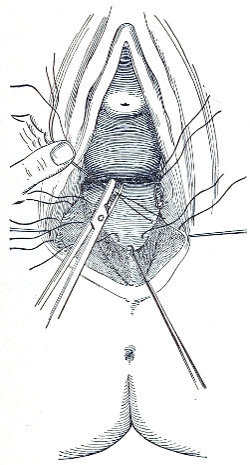

Slight Median laceration of the Perineum.—In this injury the tear takes place through the fourchette. Posteriorly it may extend as far as the sphincter ani muscle. Upward it may extend for an inch up the posterior vaginal wall. The appearance of this tear is shown in Fig. 33. It will be noted that, as this tear takes place in the median line, none of the muscles that support the perineum are involved, nor are the planes of fascia injured. The perineum is slightly split, and the insertions and origins of the muscles and the fascia are slightly separated. The supporting structures of the perineum and the pelvic floor are, however, uninjured.

Fig. 33.—Recent slight median laceration of the perineum: sutures introduced.

If this tear is detected after labor, it should be closed by the immediate operation. A slight tear involving chiefly the cutaneous aspect of the perineum should be closed by three or four sutures introduced from the outside, as in Fig. 33. The needle should be introduced about a quarter of an inch from the edge of the wound. It should not be passed parallel with the plane of the lacerated surface, but should be swept outward and then inward toward the 68 angle at the bottom of the tear (Fig. 34). It may either emerge at the angle and be re-introduced, or it may be passed directly through to the skin-margin on the opposite side of the wound. If the suture is passed in this way, there will be perfect apposition throughout the whole surface of laceration. If the sutures are improperly passed, there may result only apposition of the skin-edges.

Fig. 34.—Diagram representing the correct and the incorrect method of passing the suture for closure of slight perineal laceration.

If the laceration extends up the posterior vaginal wall, two sets of sutures must be introduced—one on the vaginal aspect of the tear, and one on the skin aspect (Fig. 35).